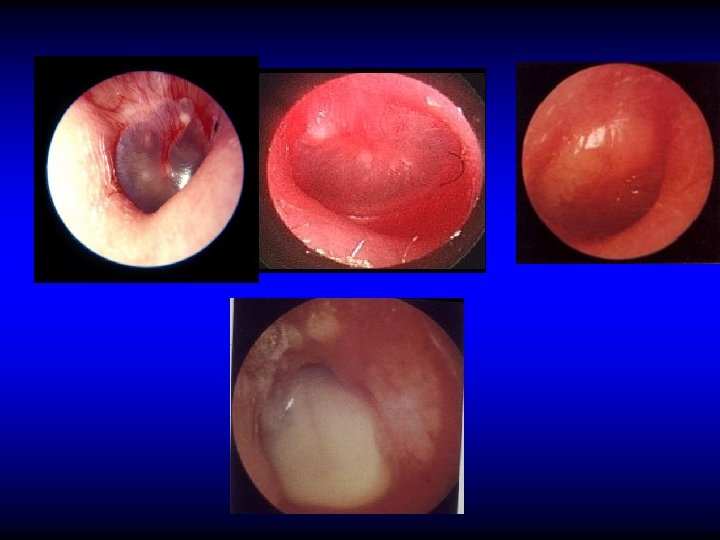

Otoscopic examination • Discharge – Present in TT type if active but may be absent – Usually is present in AA type • Perforation – Central: in TT type – Marginal or attic in AA type with cholesteatoma

Perforation in TT CSOM

Perforation in AA CSOM

Otoscopic examination • Discharge – Present in TT type if active but may be absent – Usually is present in AA type • Perforation – Central: in TT type – Marginal or attic in AA type with cholesteatoma • Polyps, granulation tissue, tympanosclerosis